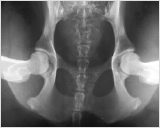

2. Kompression

Die Lagerung erfolgt wie in 1, nur werden diesmal die Gelenkköpfe des Femurs sanft in die Gelenkpfanne positioniert.

In dieser Ansicht können pathologische Veränderungen am Gelenk identifiziert werden. Ebenso ist es möglich zu prüfen, wie akurat der Gelenkkopf in die Gelenkpfanne passt.